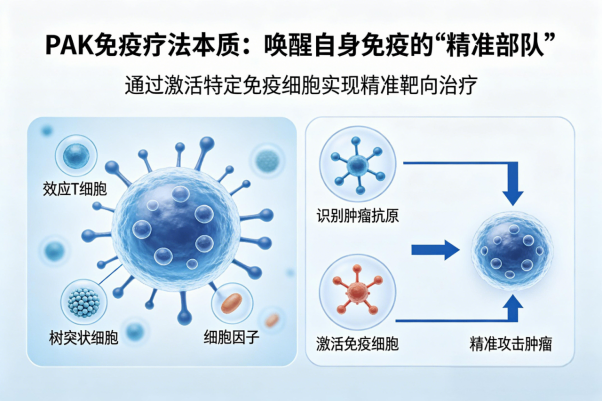

生物新技术

NK免疫疗法

NK免疫疗法

3

RAK免疫疗法

RAK免疫疗法

4

加强型免疫疗法

加强型免疫疗法

5

六大核心业务

国际领先六大肿瘤疗愈体系,确保每一位肿瘤患者得到超越预期的肿瘤疗愈,康复,终身健康保障服务。中美国际肿瘤连锁:郑州誉美肿瘤医院,武汉名逸肿瘤医院、博鳌华侨肿瘤医院。